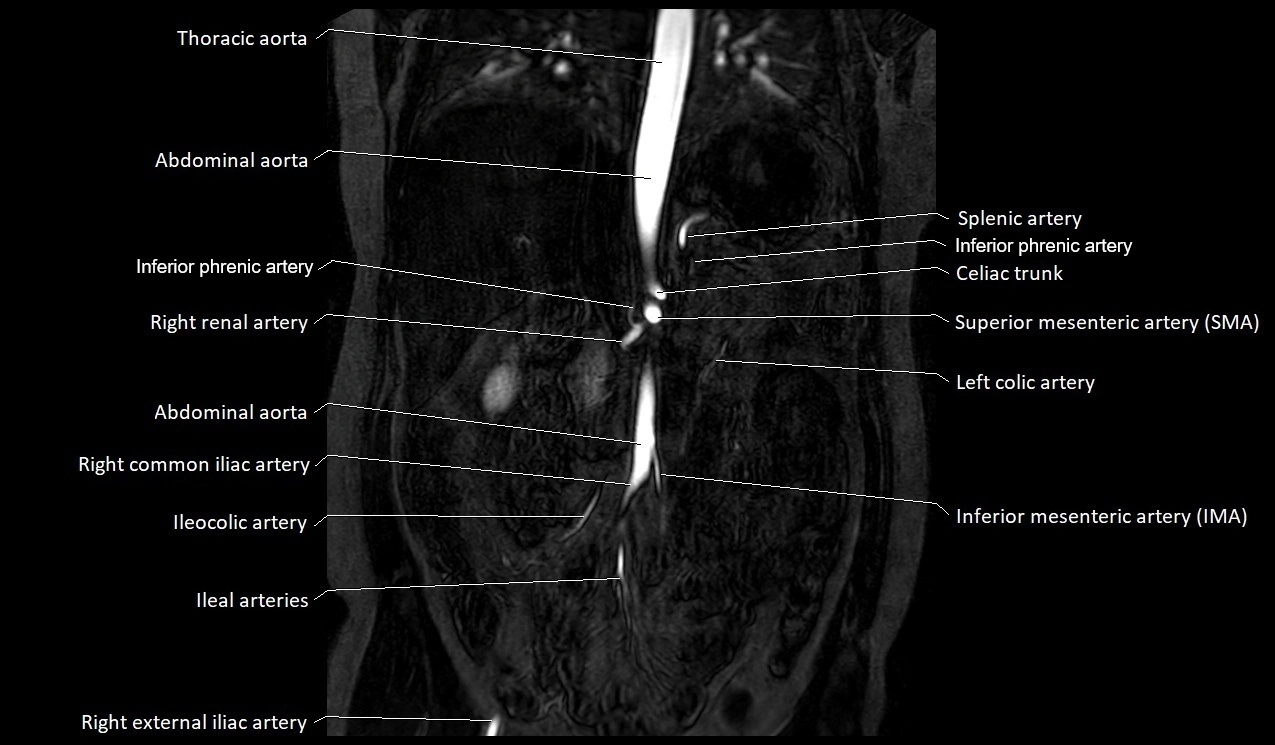

MRI Appearance

T1-weighted images:

Artery appears as a small linear hypointense flow void coursing over the superior pubic ramus

Seen within bright perivascular fat of pelvis

MRA Pelvis with Gadolinium:

Clearly delineates the origin, course, and anastomoses of the accessory obturator artery

Identifies connection with inferior epigastric artery, external iliac artery, or obturator artery

Excellent for detecting vascular variants prior to surgery

Useful in mapping pelvic vasculature in trauma, tumor embolization, or preoperative planning